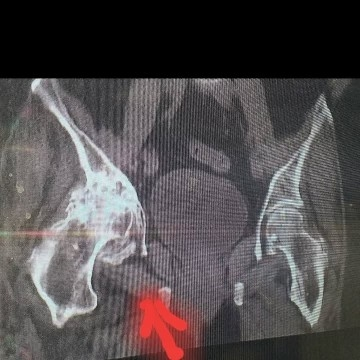

عکس های قبل و بعد از عمل خانم 64 ساله که استئوارتریت ( آرتروز ) شدید در مفصل هیپ راست با تغییرات مثبت در سی تی اسکن

با درد و محدودیت حرکتی شدید مفصل هیپ راست همراه با لنگش و کوتاهی در اندام تحتانی راست و ناتوانی در راه رفتن که تحت عمل جراحی تعویض مفصل هیپ راست از نوع دوال موبیلیتی آرتروپلاستی قرار گرفتند .